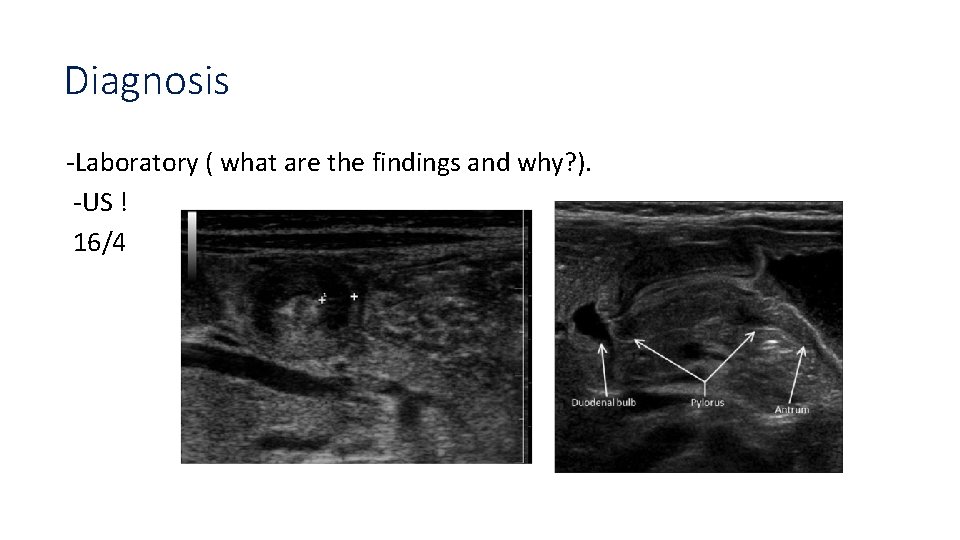

Case 3: You are working in the ER, a mother brings her 5 weeks old child, complaining of projectile white colored vomiting, started 2 days go, progressively increasing, now occurring after each feeding. -What’s the most probable diagnosis? Pyloric stenosis. -is it congenital or acquired? Acquired ! - What to find on examination?

Olive mass visible peristalsis

Diagnosis -Laboratory ( what are the findings and why? ). -US ! 16/4

Erect abdominal xray Double track sign string sign

Management -Stop oral feeding. -Correction of hydration (150 ml/kg of 0. 45% NS + 20 meq of KCl in 1 liter fluid) -Surgery is not an emergenry. (pyloromyotomy).